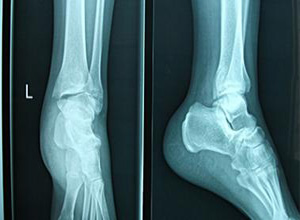

13岁孩子骑自行车摔了一下,造成左桡骨远段骨皮质断裂,侧位示断端错位

[image]10 左腕三角骨骨皮质断裂,骨小梁连续中断,骨折线稍模糊,关节

崴伤,左侧第5跖骨近段骨皮质连续性中断,是静养,还是采取手术?